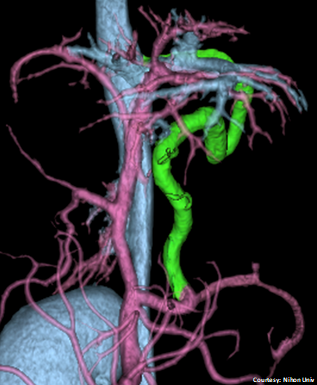

“LGC +RGV”

“LGC +RGV +SGV”

Left Gastro-Caval Shunt with Right Gastric Vein and Short Gastric Vein contributions

Courtesy: Nihon Univ